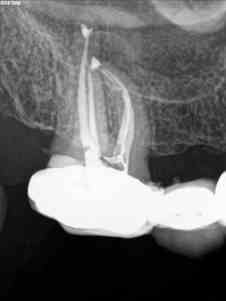

B) Un 1.6 con una pulpitis irreversible.

B)